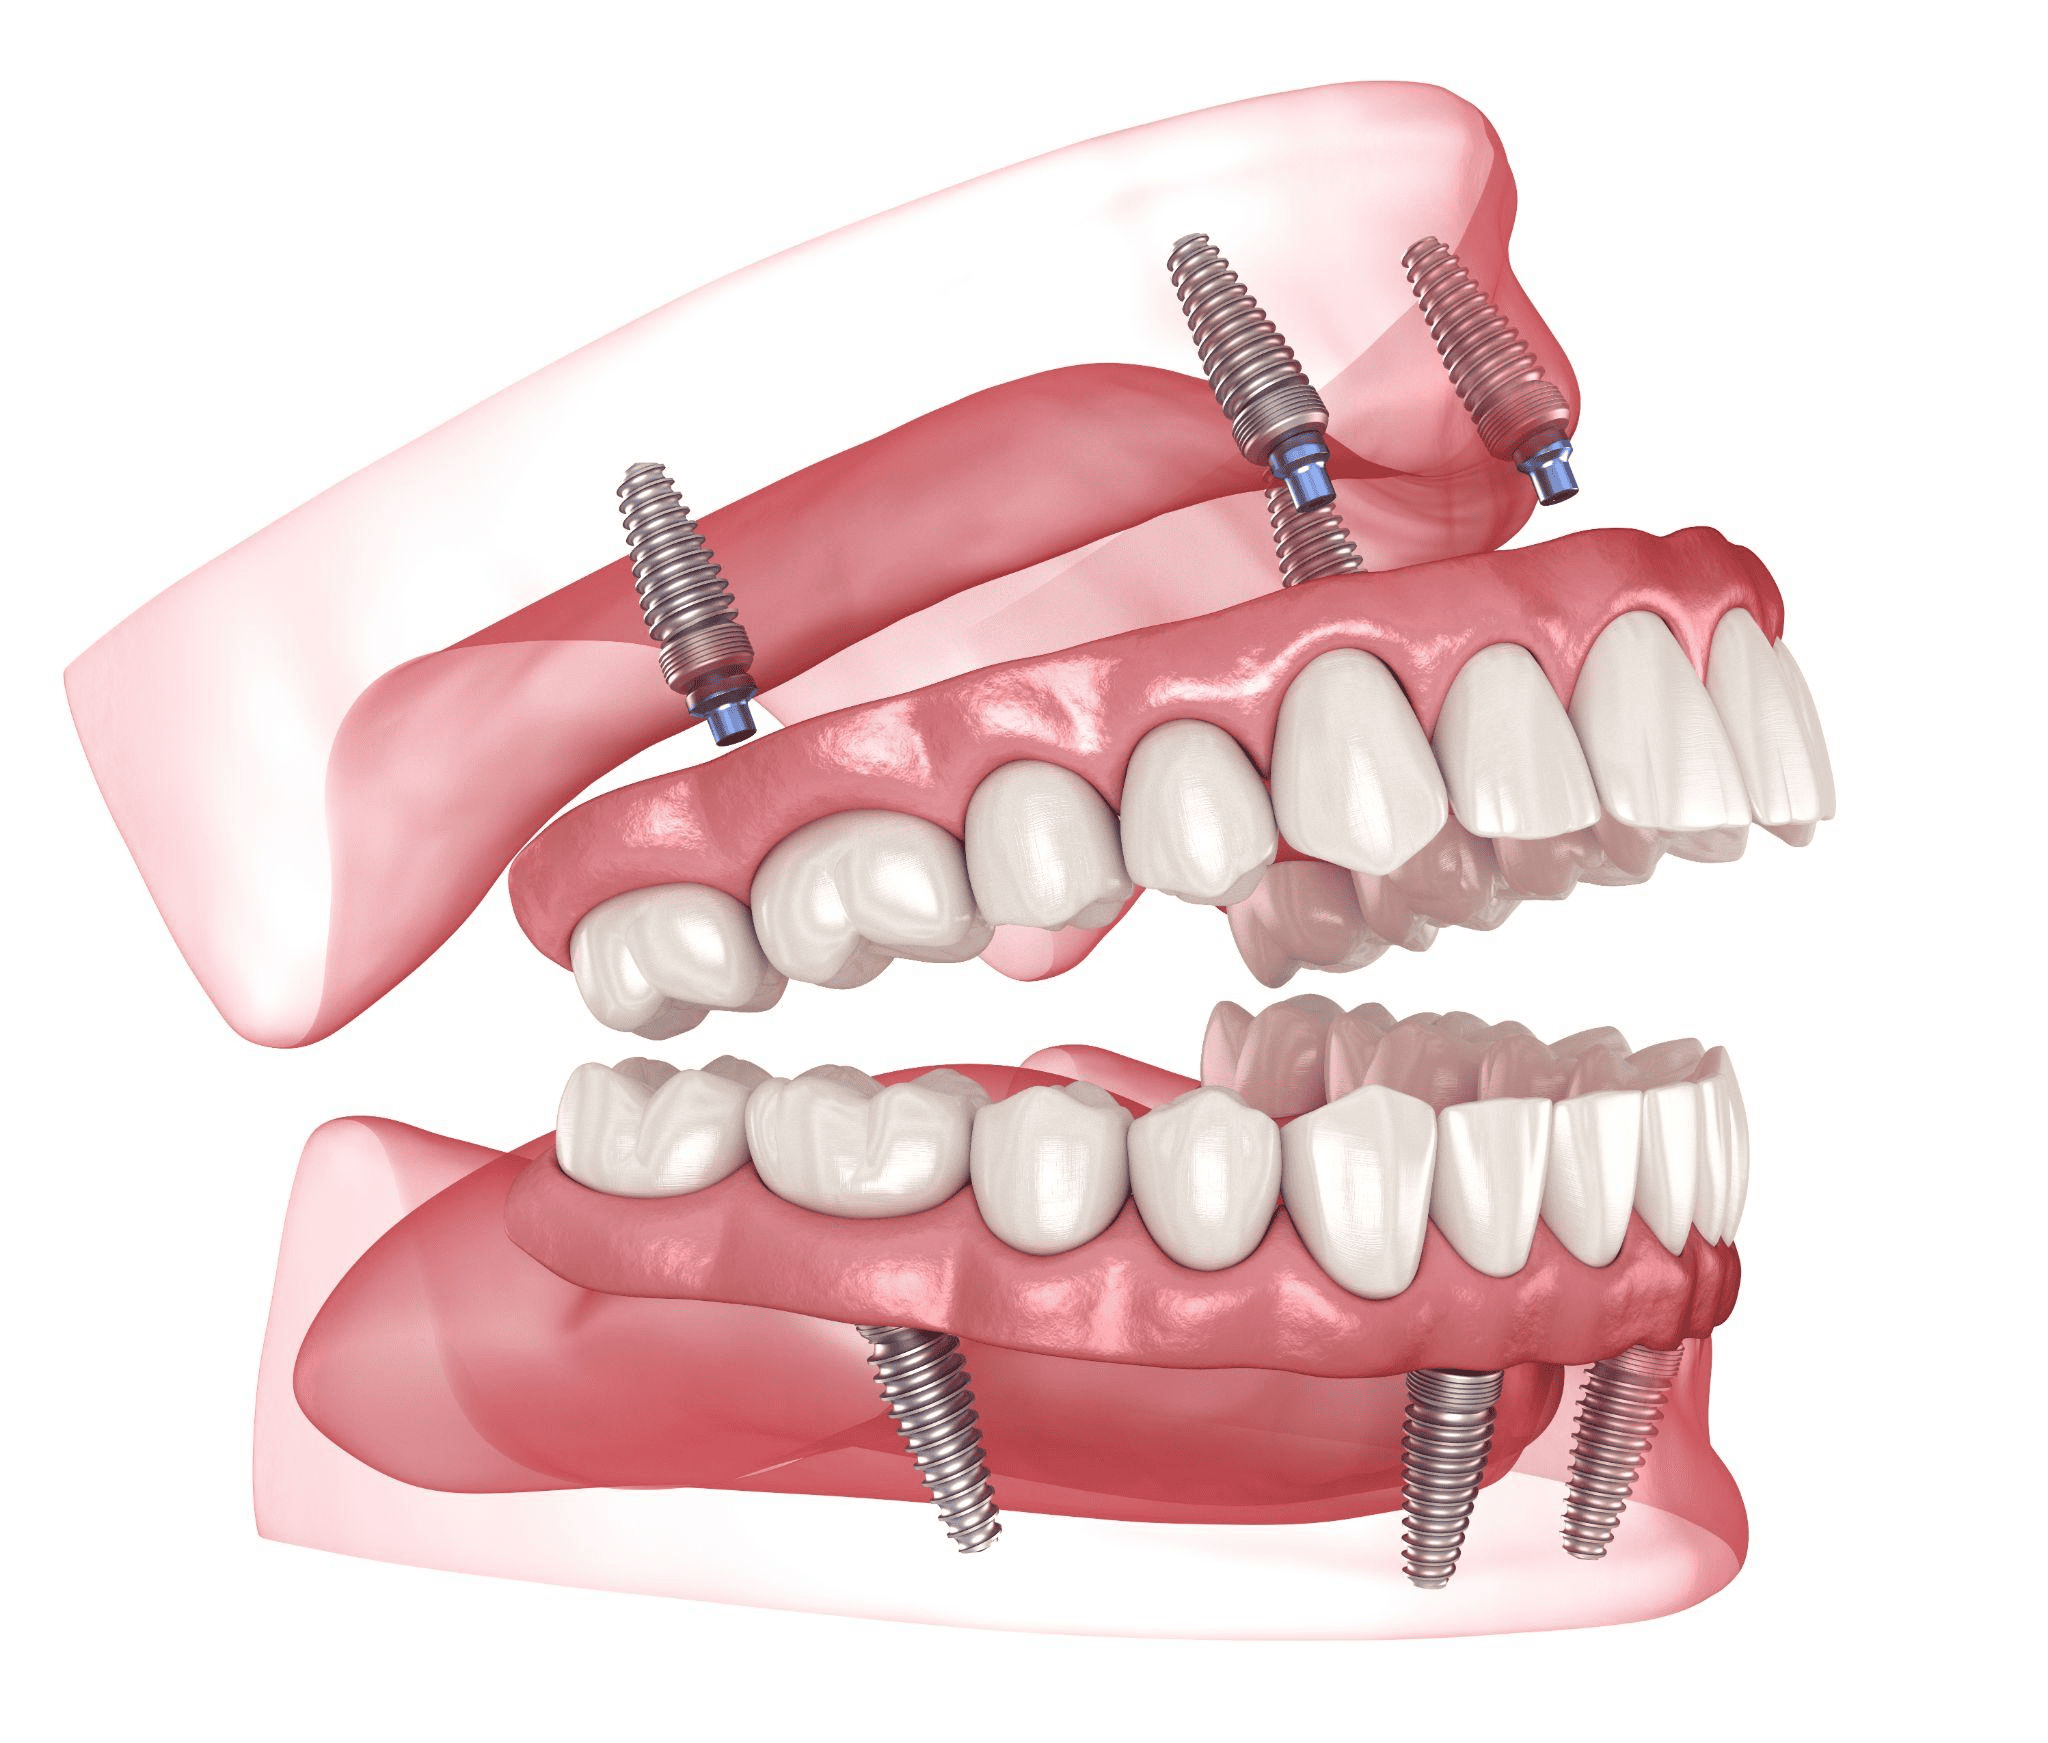

インプラントとは

インプラントは失った歯の部分に人工歯根を埋入し、上部に人工歯を装着して噛む機能を回復させる方法です。

自然な見た目や自分の歯のような噛み心地を希望する場合に検討される治療で、歯を失った方から注目を集めています。

ここでは、インプラントのメリットや注意する点などについて紹介します。

インプラントのメリット

インプラントは人工歯根を骨に埋め込むため安定性が高くなる特徴があり、さまざまなメリットがあります。

以下がインプラントの代表的なメリットです。

- 周囲の歯を削らずに装着できる

- 強く噛み締められる

- 見た目が自然で審美性が高い

- 顎の骨が痩せづらくなる

インプラントは周囲の歯を削らない治療のため、健康な歯にダメージを与えず、口腔の健康を保ちやすくなっています。

強い力で噛み締めることや審美性の高さ、インプラントによる刺激で顎の骨が痩せにくくなるなど、生活の質を維持しやすいこともメリットです。

インプラントでブリッジを支える方法を選ぶ

インプラントの費用を抑えたい場合、「インプラントブリッジ」という治療法を選択するのもおすすめです。

インプラントブリッジとは、数本のインプラントを支柱として埋め込み、ブリッジをかける方法です。

インプラントの費用は使用するインプラントの本数で変わりますが、インプラントブリッジで本数を減らせば費用の軽減につながります。

複数の歯を失っていてもインプラントブリッジで対応できるケースがあるため、気になる方は医師と相談してみてください。